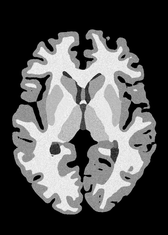

4.2 Registration to a 100 micron ex-vivo brain MRI volume

To showcase the efficacy of our method on real large scale images, we register a 250 in-vivo MRI image (Lüsebrink et al., 2017) to a 100 ex-vivo FLASH human brain volume (Edlow et al., 2019). This represents an inverse problem with more than 11.2B optimizable parameters (compared to 20M for clinical datasets), or 44.8GB of GPU memory. The entire problem does not fit on most GPUs, necessitating distributed multimodal registration. We optimize a composite transform - affine followed by a diffeomorphic mapping; details can be found in Section E.1. Multimodal deformable registration took 58 seconds on 8 NVIDIA A6000 GPUs, which is unprecedented at this resolution. Fig. 6 shows qualitative results, highlighting the ability to register highly detailed structures such as cerebellar white matter; these structures are not visible at macroscopic scales. The resultant advantages of performing registration at this scale can allow researchers to characterize the neuroanatomy at microscopic resolutions and allow morphometric analysis of cortical layers and subcortical nuclei among other structures.